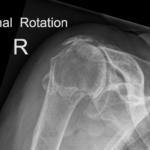

Shoulder arthritis can develop in two main patterns, one where there is no known cause and secondly can be as a long term consequence of a torn rotator cuff resulting in rotator cuff arthropathy.

It can lead to pain, stiffness and sometimes a “creaking” or “crunching” in the movements of the shoulder.